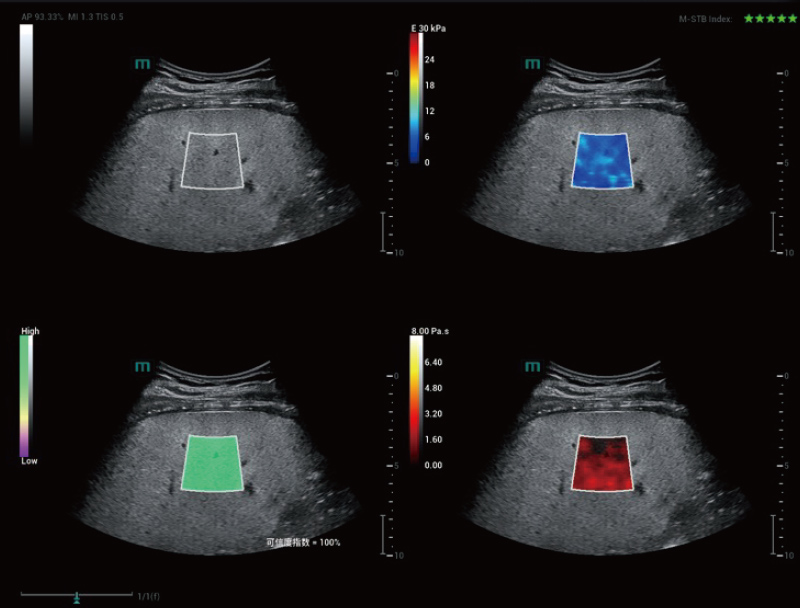

STVi enables the quantitative evaluation of tissue viscosity and

provides real-time multi-parameter imaging, offering a more

comprehensive approach to imaging diagnosis and quantitative

analysis of chronic liver diseases, breast lesions, and other

conditions.

Dual quantitative coefficients

Chronic liver disease assessment

Multiple quantification tools

Breast tumor assessment